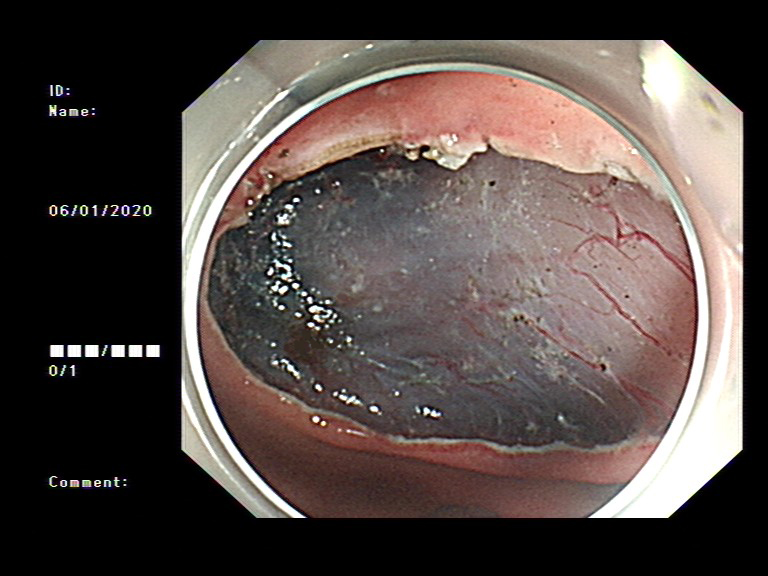

2020年1月,元旦刚过,大家都还沉浸在新年的喜悦中,来自隆安县的张阿姨一家却一筹莫展,张阿姨今年55岁,半年前开始出现上腹部胀痛不适,在当地医院一直按“慢性胃炎”服用中药及西药治疗,症状时好时坏。为了进一步治疗,来到我院就诊,内镜中心袁海锋主任亲自为其进行了无痛胃镜检查,经认真仔细观察发现胃内一处凹陷型病变,进一步行精细胃镜检查后,初步判断为早期胃癌病灶,而且病变侵犯深度局限在粘膜层内。经过与张阿姨及家属详细沟通后,决定用内镜下微创手术为其治疗。在内镜下确定病变边界后,顺利行内镜下粘膜剥离术(ESD)将病变完整切除。术后标本病理提示:早期胃癌(中分化管状腺癌)。治疗后一周,恢复良好,顺利出院,至今随访未诉明显不适。对于张阿姨一家来说,得了胃癌很不幸,但不幸中的万幸,她的胃癌被我们早期及时发现并完成了内镜下切除,避免进展为中晚期胃癌,使原本不富裕的家庭再雪上加霜。

图1 胃镜下早癌病灶